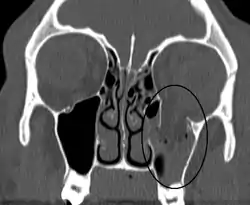

![]() كسر انفجاري محجري في أرضية محجر العين الأيسر. كسر انفجاري محجري في أرضية محجر العين الأيسر. | |

كسر أرضية الحجاج أو كسر أرضية المحجر أو الكسر الانفجاري (بالإنجليزية: Orbital Blow-out Fracture) والحجاج هو التجريف العظمي المحيط بالعين وينتج عن رض أمامي لكرة العين أو حادث سير أو أي حادث ناتج عن ارتطام الوجه بشئ صلب، وينتقل الرض بشكل إجباري لقاعدة الحجاج العظمي الضعيفة فتنكسر، ويمكن تشخيص كسور عظام الحجاج بعمل اشعة مقطعية أو عمل رنين مغناطيسي على الحجاج أو حتى الصورة الاشعاعيه البسيطه ذلك حتى نكتشف مكان الشرخ أو الكسر العظمي وكذلك معرفة عضلات العين المحشورة داخل هذا الكسر، وتؤدي بعض اصابات الحجاج إلى شرخ أو كسر في هذه العظام فتنحشر عضلات العين داخل هذا الشرخ أو الكسر وتصبح عاجزة عن تحريك العين واكثر العضلات تأثراً من اصابات عظام الحجاج هي العضلات السفلية ويؤدي احتباس العضلات السفلية داخل الكسور العظمية إلى عدم قدرة العين إلى الحركة إلى أعلى ويلاحظ على هؤلاء المرضى أنهم عندما ينظرون إلى أعلى فإن العين السليمة تتحرك إلى أعلى بينما العين المصابة فلا ترتفع، وقد يهبط بعض مكونات المحجر والشحم أو العضلة المستقيمة السفلية إلى جوف الجيب الفكي، الكسر يؤدي لغؤور العين وتحدد حركاتها وقد يحدث شفع بالابصار.[1][2][3]